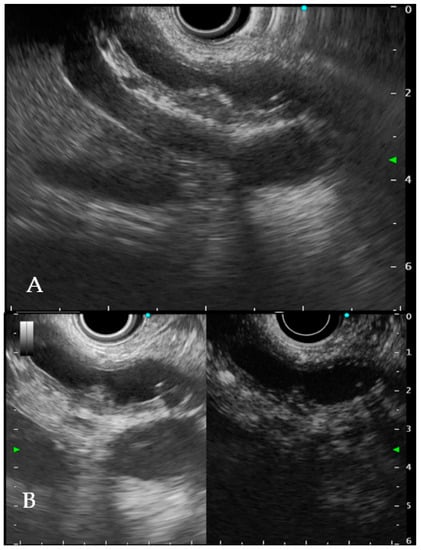

6.1. Intraductal Ultrasonography

6.2. Endoscopic Ultrasound

- Sun, B.; Hu, B. The role of intraductal ultrasonography in pancreatobiliary diseases. Endosc. Ultrasound 2016, 5, 291–299. [Google Scholar] [CrossRef]

- Meister, T.; Heinzow, H.S.; Woestmeyer, C.; Lenz, P.; Menzel, J.; Kucharzik, T.; Domschke, W.; Domagk, D. Intraductal ultrasound substantiates diagnostics of bile duct strictures of uncertain etiology. World J. Gastroenterol. 2013, 19, 874–881. [Google Scholar] [CrossRef]